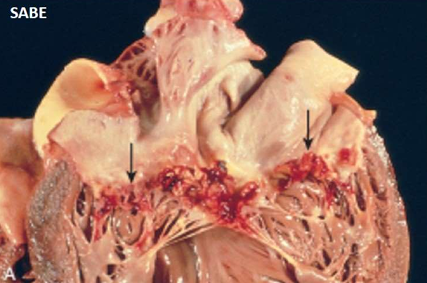

Bacterial INFECTIVE Vegetations

SABE = on diseased valves

ABE = on normal valves

LARGE, green tawny, irregular, single/multiple, TYPICALLY FRIABLE

SABE Non RH Endocarditis: Infective Bacterial

- valve thickened and fibrotic

- firm, gray vegetations

- organized

- sometimes may show calcification

- chronic inflammatory granulation

- healing scars